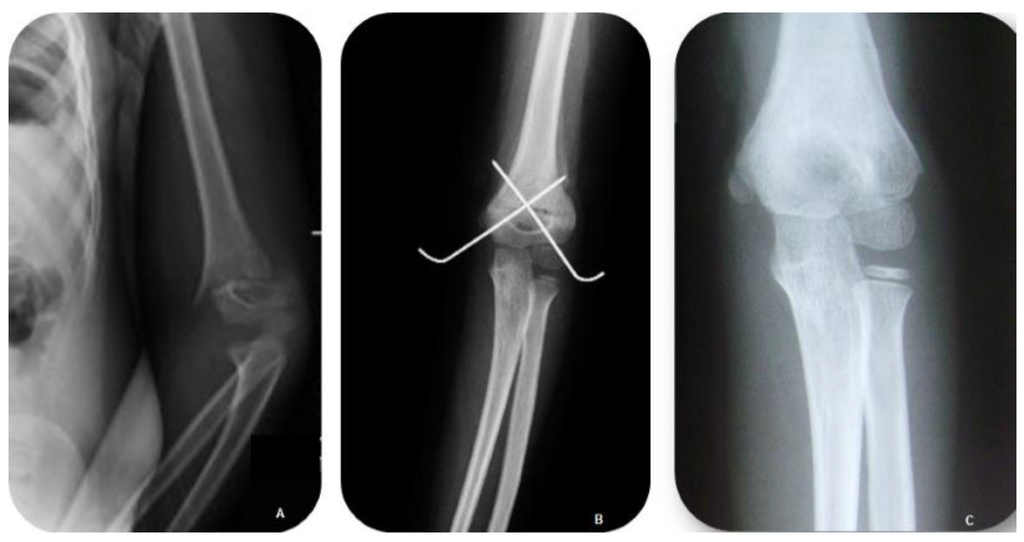

Surgical Treatment of Displaced Supracondylar Pediatric Humerus Fractures: Comparison of Two Pinning Techniques

2. Patients and Methods

3. Results